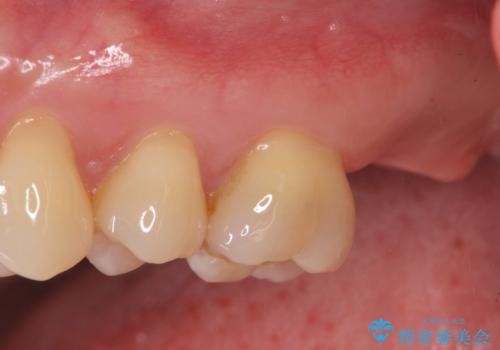

歯の破折で抜歯を余儀なくされ、ショックが大きかったですが、しっかりとインプラントで咬合機能が回復することができ、喜んでいただくことができました。